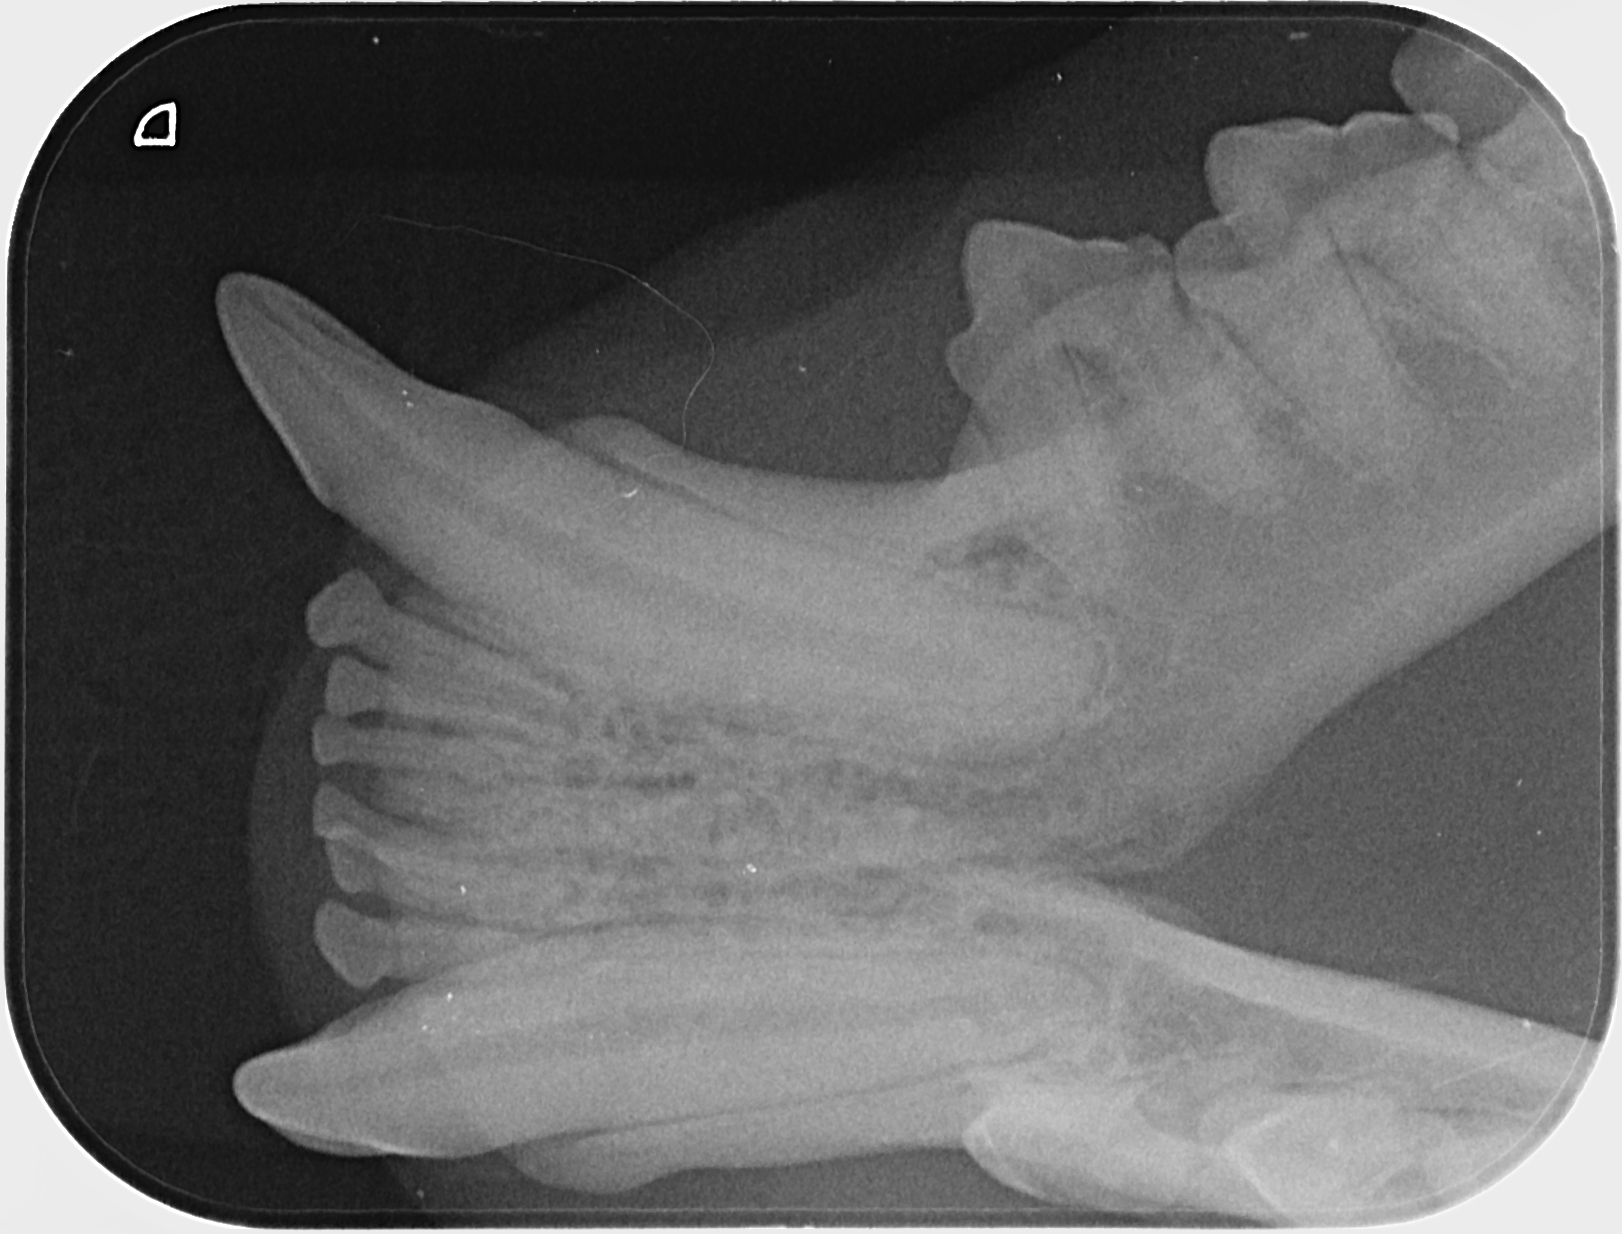

Kissan hampaat voivat näyttää päällisin puolin ihan hyvältä, mutta hampaiden juurissa voi olla piileviä ongelmia. Ainoa tapa selvittää, ovatko hampaat oikeasti kunnossa, on ottaa hammasröntgen.

IC Moggi Sikuri Sakari(Kilju) piipahti jo jonkin aikaaa sitten Amyvetissä hammahuollossa ja samassa kalusto pääsi kuviin. Tulos oli juuriaan myöten terveet hampaat. Hammaskiven poistoa pienesti ja ohjeeksi harjailla hampaita ahkerasti.

Ohessa muutama kuva malliksi.